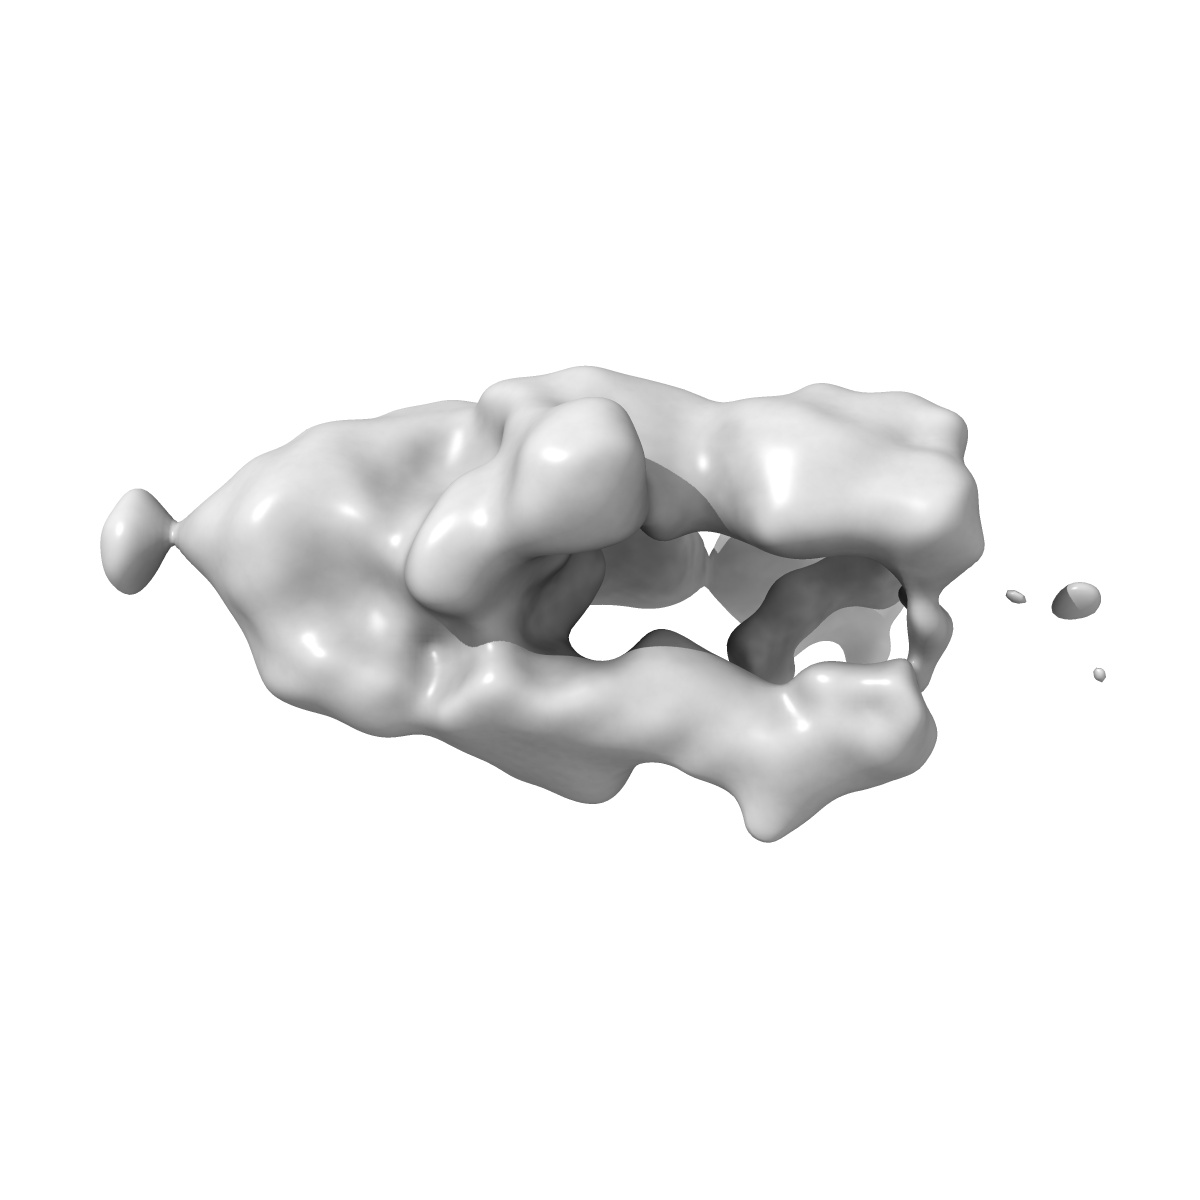

Negative stain EM map of SARS-CoV-2 Spike in complex with CoVIC-260

Single-particle20.0 Å

Sample: SARS-CoV-2 D614G HexaPro Spike in complex with CoVIC-260